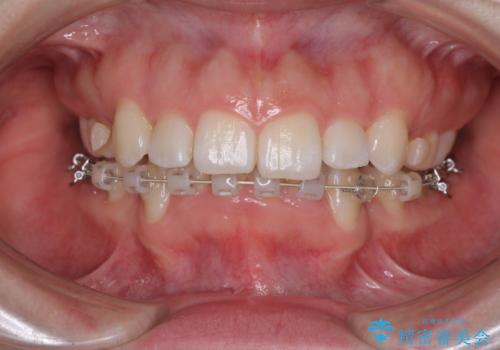

目立たない裏側矯正 抜歯矯正で口元を改善

- ハーフリンガル

- 前歯のデコボコと上顎の前突感による口の閉じにくさを気にして来院された患者様です。

目立たない装置を希望されたので、上顎が裏側装置のハーフリンガルを選択し、上下左右の小臼歯(計4歯)を抜歯して矯正治療を行うこととしました。

治療期間の目安は2年半~3年間でしたが、咬み合わせにより上顎装置が頻繁に脱落してしまい、治療期間が長期化してしまいました。

期間はかかったものの、口元の張り出し感や歯のデコボコが解消され、患者様には大変満足していただけました。